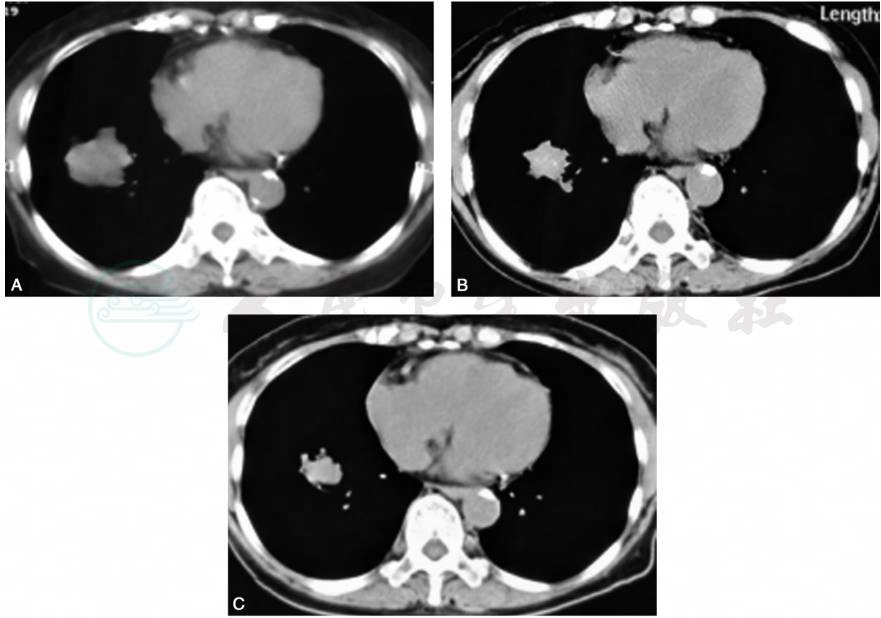

患者用药1个月后咳嗽、咳痰明显好转,CEA降至正常;复查胸部CT(图5)示肿块缩小约41.6%,按照RECIST标准,肺癌部分缓解(PR)。患者口服吉非替尼后的PFS为11个月,总生存期为15个月。

图5吉非替尼治疗前后病灶变化,提示吉非替尼治疗有效,病灶逐渐缩小,部分缓解(PR)

A.吉非替尼治疗前(2018年1月1日)肿块 4.3cm×4.1cm;B.口服吉非替尼2个月后(2018年2月24日)肿块2.7cm×2.9cm;C.口服吉非替尼4个月后(2018年4月3日)肿块2.3cm×2.6cm